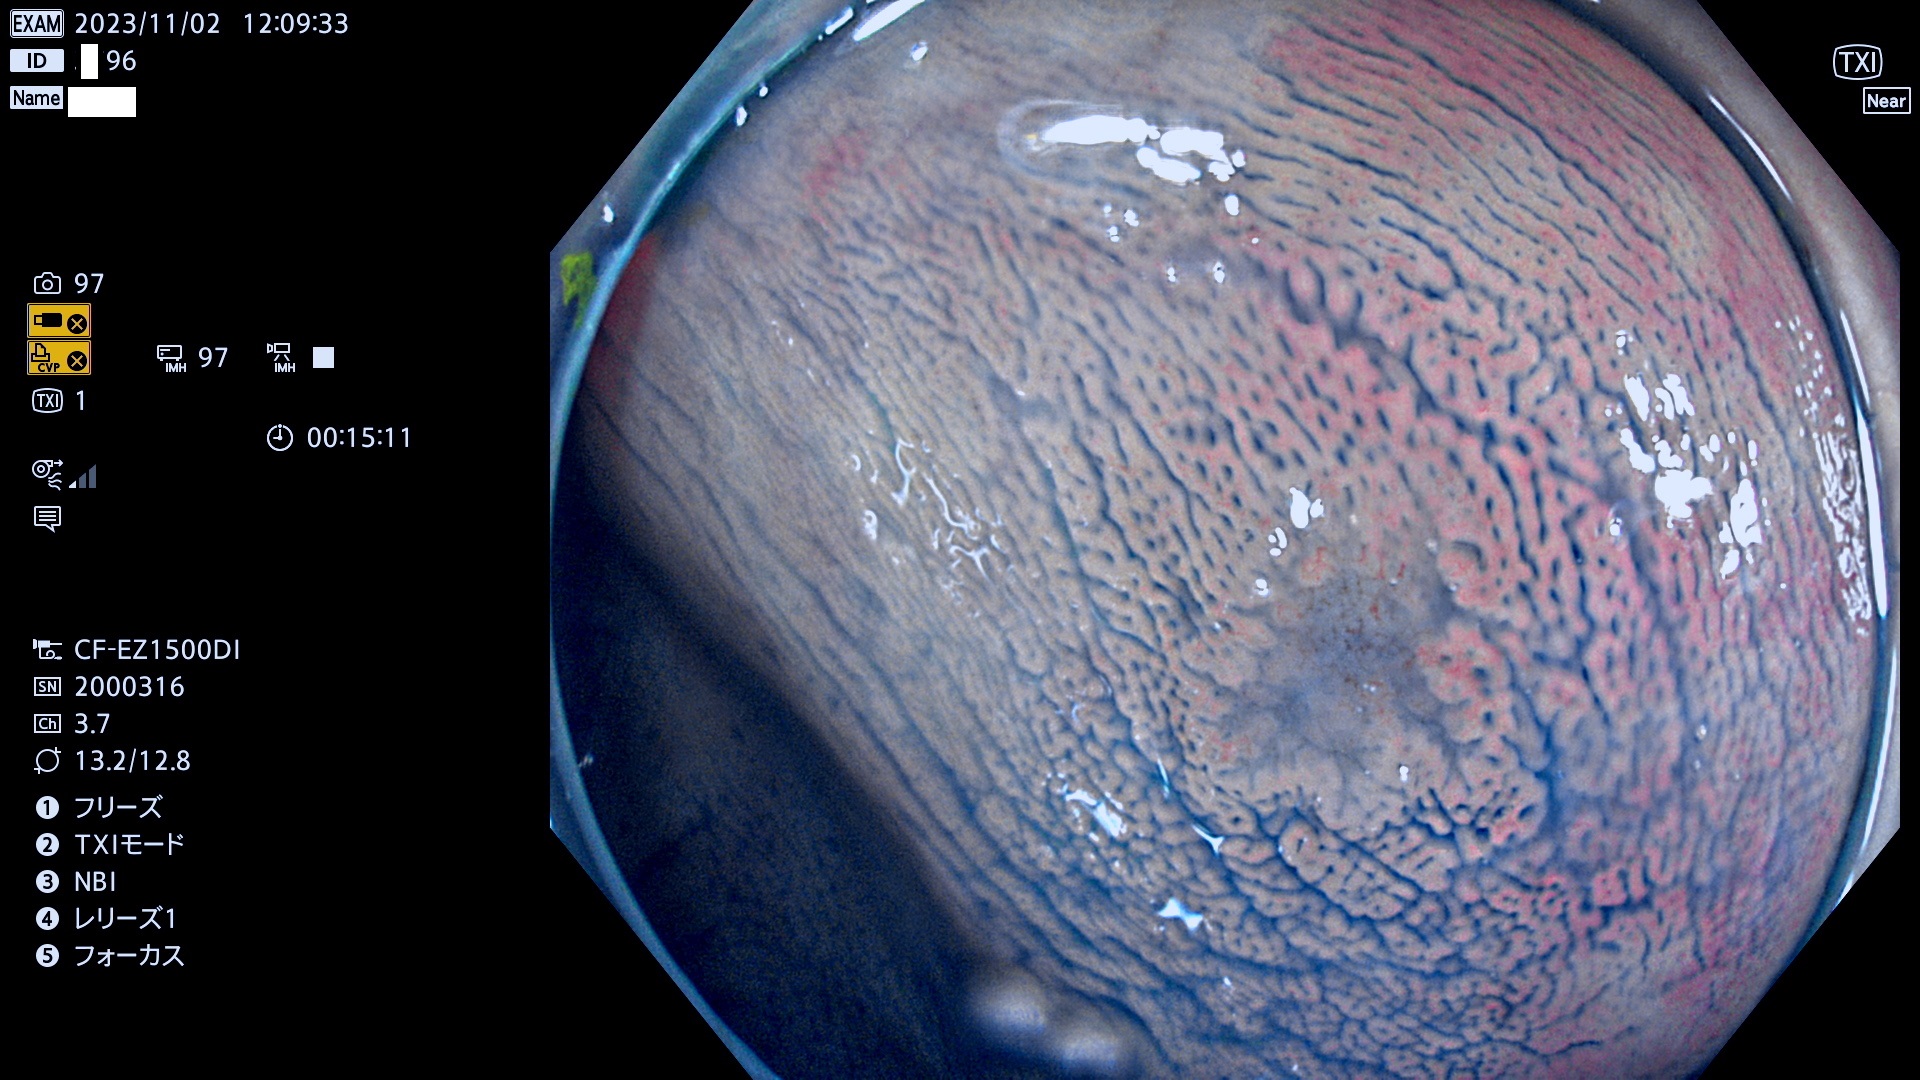

表面型腺腫(Flat Adenoma)の中で、完全に平坦な物をUb、陥凹している物をUcと呼びます。平坦隆起型(Ua)よりも、発見が難しく危険な病変です。このタイプは「内視鏡後・大腸癌の重要犯人」であり、この発見率は「腺腫発見率」よりも、重要な意味があります。

毎週の検査(木・金・土・日)に発見されたUb、Uc型・腺腫を、その週の日曜の夜にUPし1週間、提示します。

抽出の対象期間 2023年11月2日(木)〜11月6(月)の5日間(60件の検査)11件